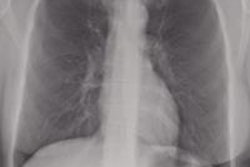

The team then compared the observer and CAD marks with the reference standard of CT studies. The combination of bone suppression software and CAD yielded the highest reader sensitivity, while conventional chest radiography performed the worst, as indicated in the table below.